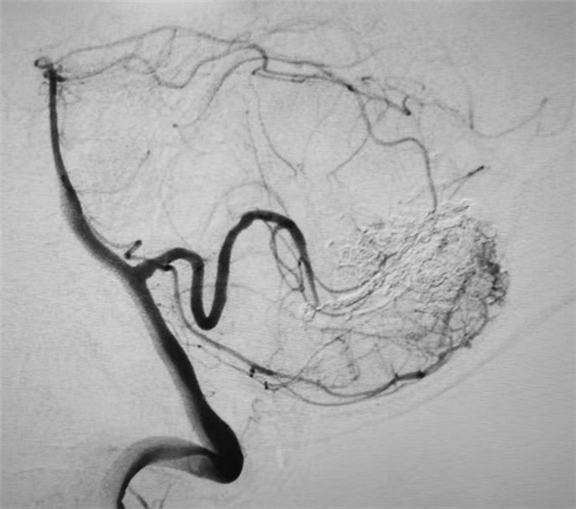

术中造影精确显示脑血管畸形合并颅内动脉瘤

栓塞术后造影动脉瘤致密栓塞,小脑畸形血管团消失,术后患者恢复良好